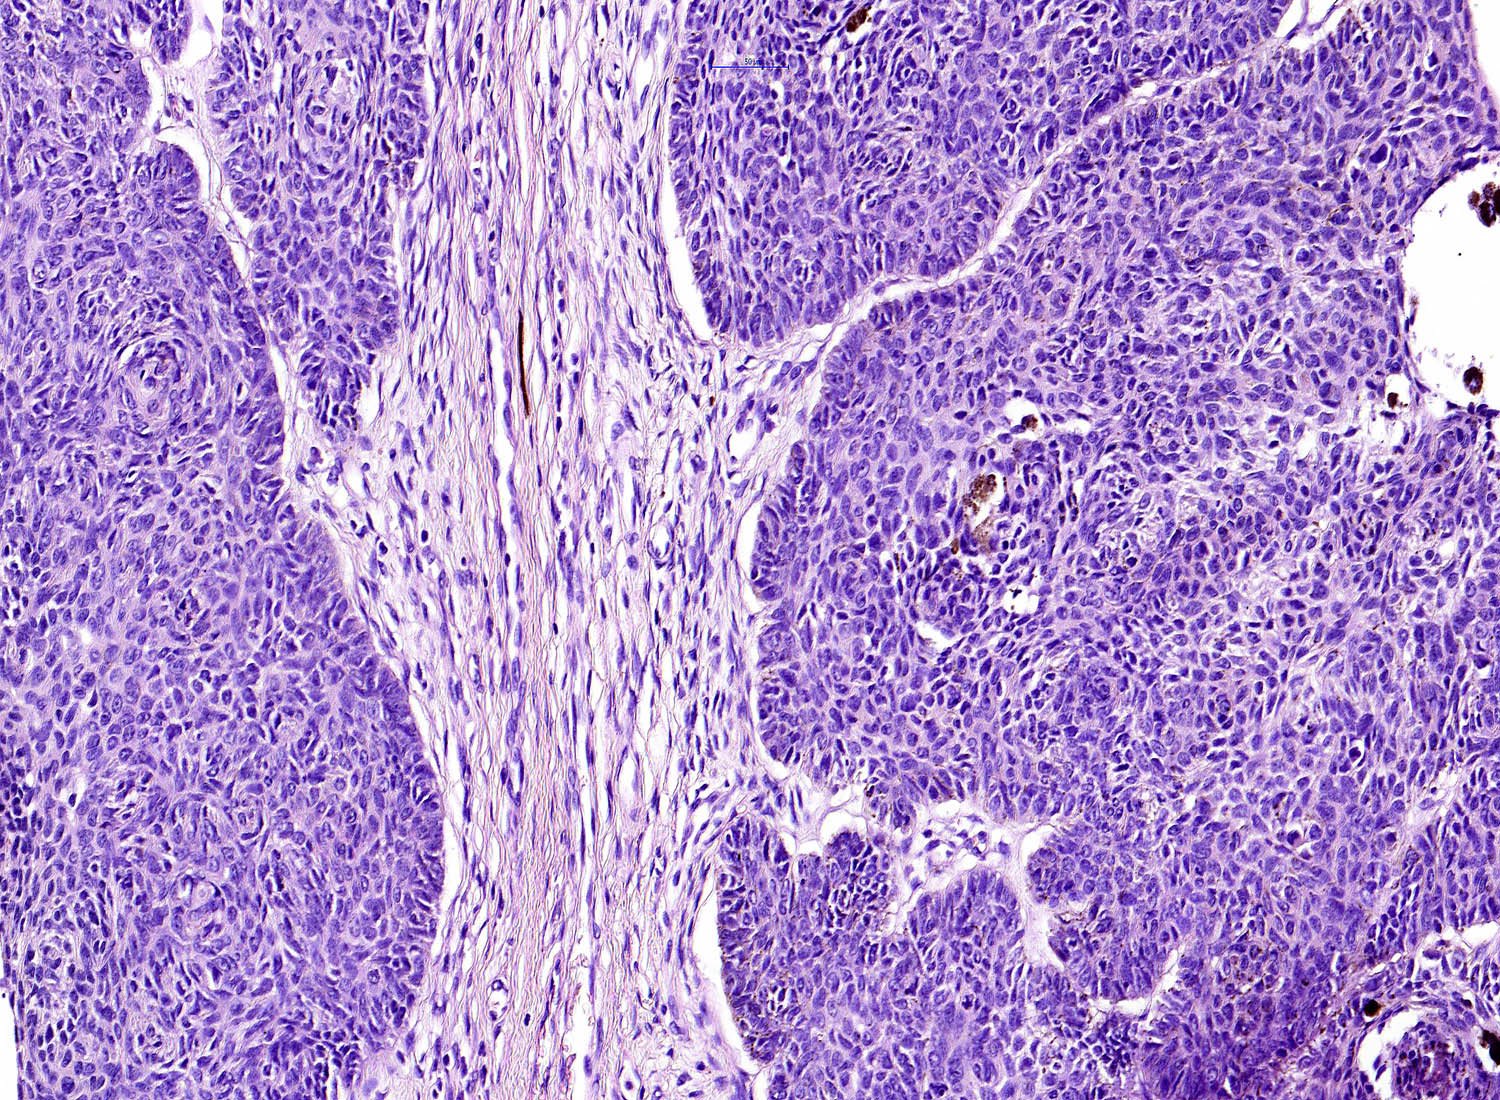

Common variants (Calonje: McKee's Pathology of the Skin, 5th Edition, 2019)

- Nodular and nodulocystic BCC

- Relatively circumscribed mass

- Epidermal or follicular attachment variably present

- Large basaloid lobules with peripheral nuclear palisade

- Lobules may be solid or show central cyst formation due to excessive mucin production

- Fibromyxoid stroma

- Cleft formation between tumor lobules and stroma

- Pleomorphism is generally mild

- Variable mitotic activity and apoptosis

- Sometimes necrosis en masse

Microscopic (histologic) images

Contributed by Antonina Kalmykova, M.D., Phillip H. McKee, M.D., Sate Hamza, M.D., Eduardo Calonje, M.D.,

Wayne Grayson, M.B.Ch.B., Ph.D., James Sampson, M.B.B.S., M.Sc. and Assia Bassarova, M.D., Ph.D.